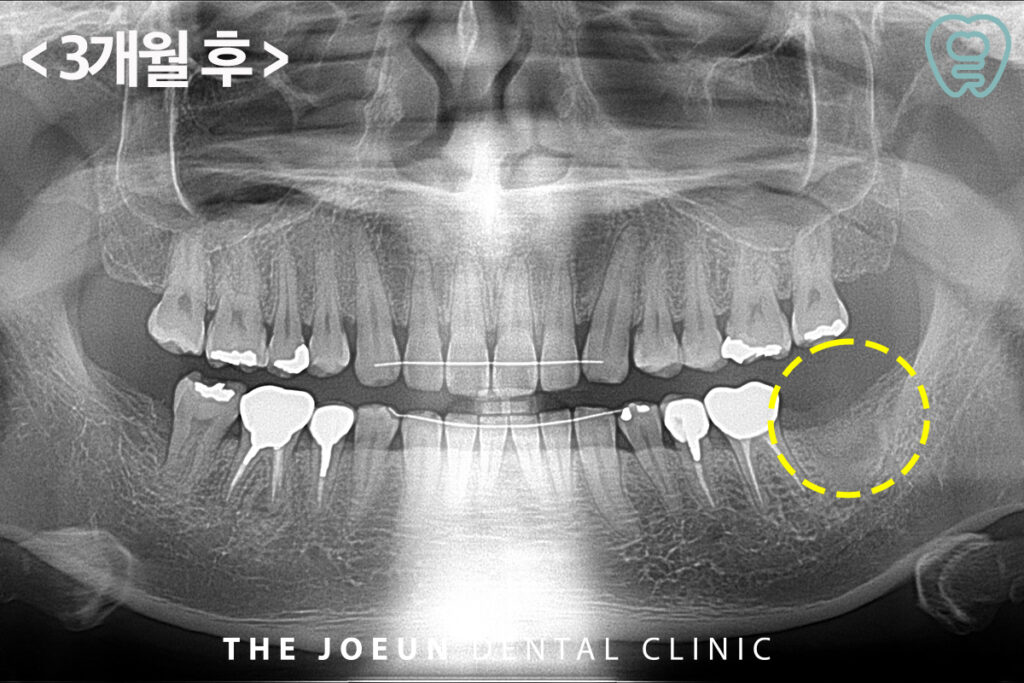

약 3개월 후의 사진입니다.

이 기간은 환자분의 체질과 회복력, 골밀도, 생활 습관에 따라 달라지므로 일정 경과 후 정기 검진을 통해 안정도를 확인하고 이식재가 치조골과 잘 결합하면 임플란트를 식립할 준비가 완료되었다고 판단합니다. 임플란트 식립은 인공치근인 픽스처를 잇몸뼈에 심고 골융합 과정을 통해 자연치와 유사한 고정력을 확보하는 방식입니다.